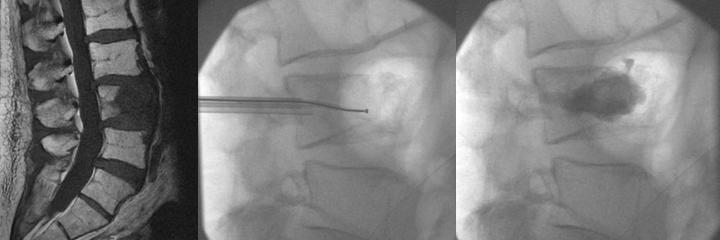

- Τέλος μπορεί να συνδυαστεί και με άλλες σύγχρονες τεχνικές όπως η θερμοκαυτηρίαση του όγκου με ραδιοσυχνότητες (radiofrequency ablation). Στις εικόνες φαίνεται η είσοδος του ειδικού probe των ραδιοσυχνοτήτων μέσα από την κάνουλα και η καυτηρίαση του όγκου (μεσαία εικόνα) και ακολουθεί η έγχυση τσιμέντου (δεξιά):